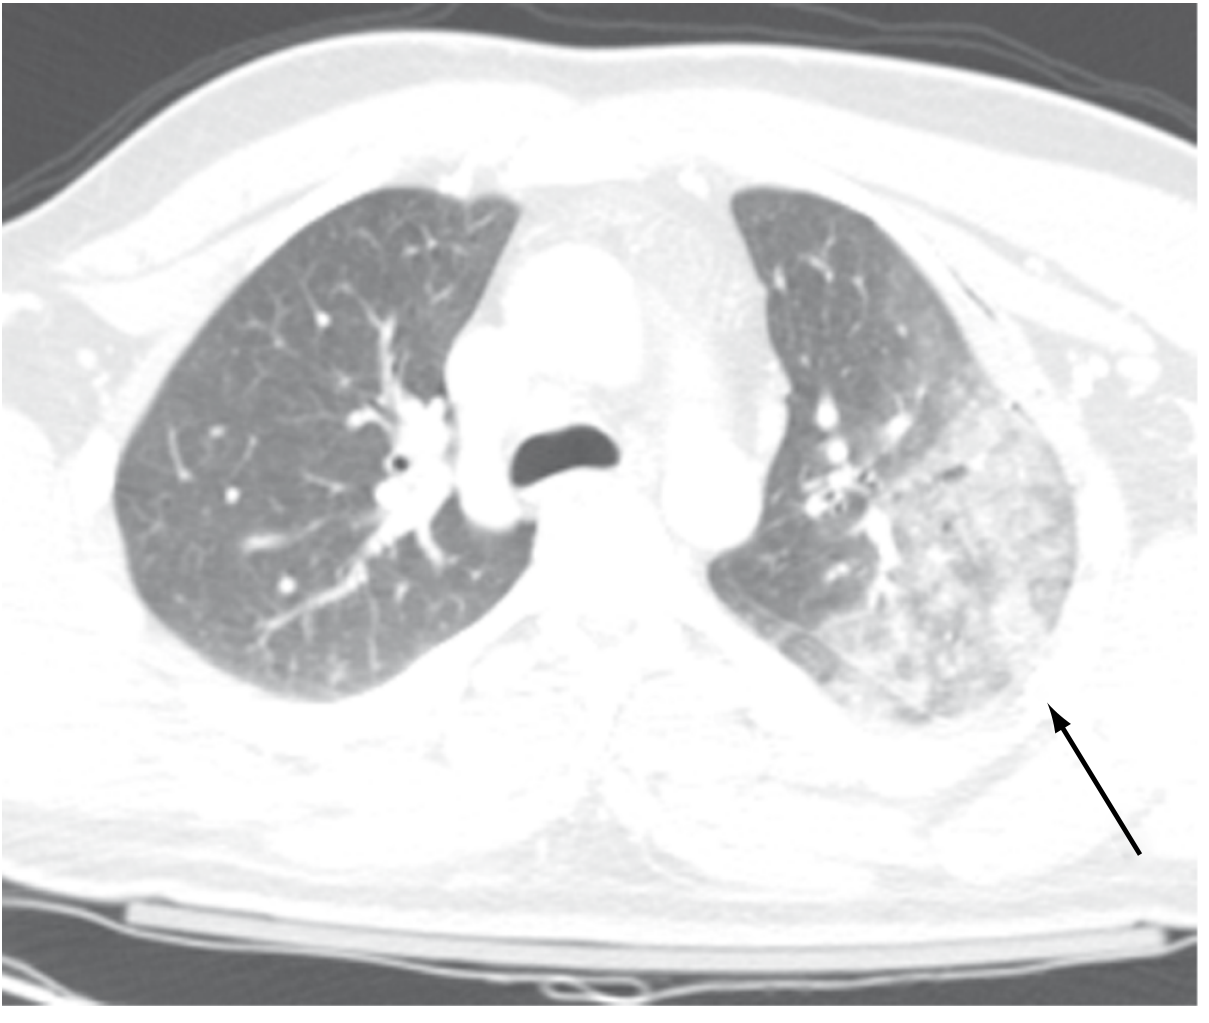

Pulmonary contusion CT

Left pulmonary contusion on CT — higher-density tissue from air-space hemorrhage — Sabiston Textbook of Surgery